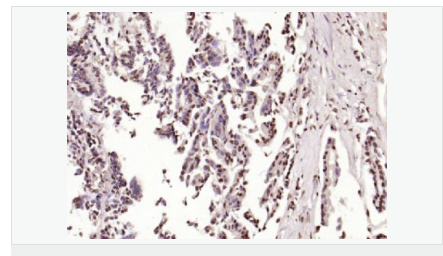

image.png